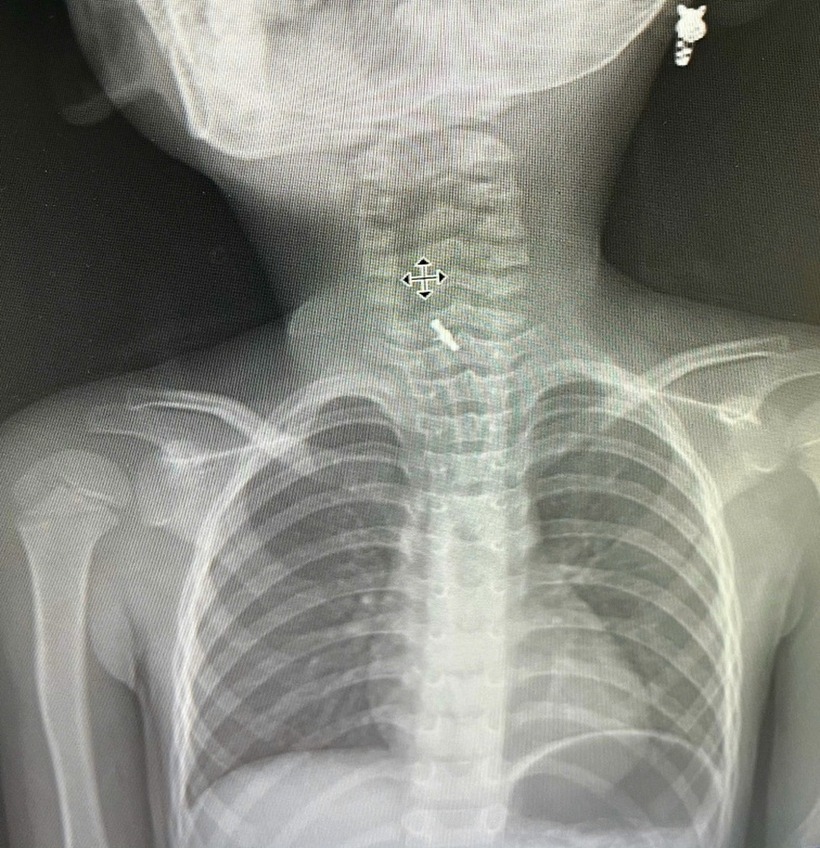

Hình ảnh chụp phim X-quang cho thấy bệnh nhi có dị vật mắc sâu trong thực quản. Ảnh: Báo Dân trí.

Hình ảnh chụp phim X-quang cho thấy bệnh nhi có dị vật mắc sâu trong thực quản. Các bác sĩ đã thực hiện nội soi bằng ống cứng và gắp dị vật ra ngoài.